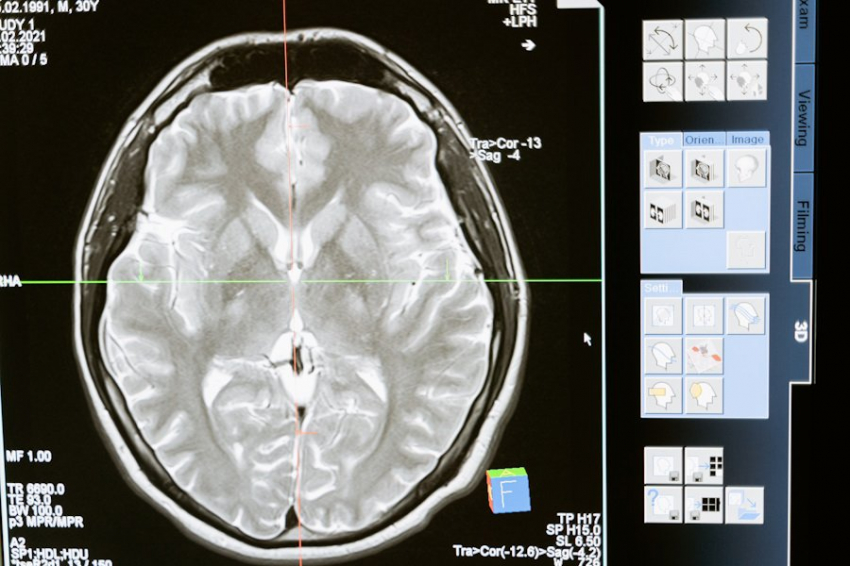

В основе устройства лежит функциональная магнитно-резонансная томография (фМРТ), которая позволяет регистрировать активность нейронов, связанных со сновидениями, сообщает Times of India.